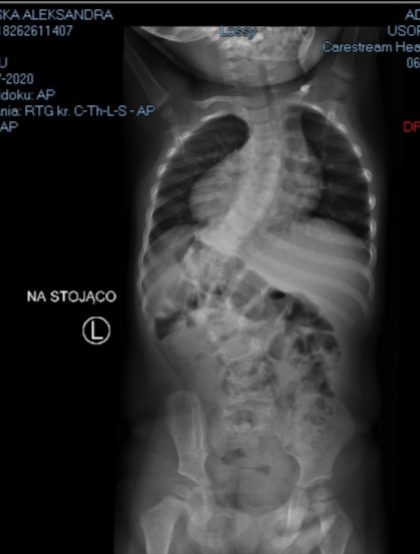

Aleksandra urodziła się w 2018 roku z zespołem wad wrodzonych, wadą serca (Zespół Ebsteina, ubytek międzykomorowy, ubytek międzyprzedsionkowy), hipoplazją lewej nerki, która pracuje w 30%, wadą rączki (rączka jest krótsza w ramieniu, przedramieniu, brak kości promieniowej, palca i kciuka) oraz ciężką skoliozą. Obecnie na chorobę serduszka Ola bierze leki, w przyszłości będzie musiała zostać wymieniona w nim zastawka trójdzielna, nereczki są pod stałą kontrolą lekarską. Za to skolioza jest na tyle ciężka, że wymaga pilnej operacji. Niestety nie każdy ośrodek w Polsce (a zwiedziliśmy ich naprawdę dużo) ma możliwość zoperowania naszej córki, z tego względu, że jest potrzebne zaplecze kardiologiczne. Lekarze boją się, że mogą wystąpić komplikacje. Udało nam się znaleźć szpital, w którym jest takie zaplecze, jednak termin operacji jest odległy. Musimy cierpliwie czekać.

Nie poddajemy się, Ola od 3 lat dzielnie przez 22 godziny dziennie nosi gorset Cheneau. Nie wyleczy on skoliozy, która ma 70 stopni, jednak daje nam szansę na to, żeby nie było większego pogorszenia, do tego dwa razy w tygodniu ćwiczy pod okiem rehabilitanta i codziennie w domu.